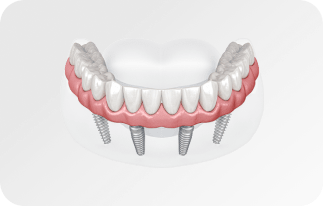

По уникальной методике

БЕЗ отёков и надрезов

Установка

за 1 день